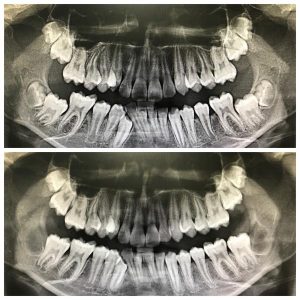

Посмотрите на снимки. Между верхним и нижним — разница в три недели. По ним хорошо заметно, что после удаления зачатков восьмёрок и «разблокировки», седьмые зубы сразу пошли в рост.